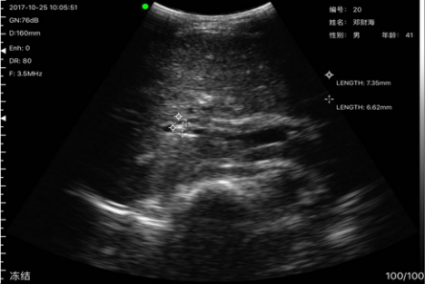

病例2姓名:刘x兰,性别:女,年龄:60岁,到我所就诊多次,但一直无法确诊具体何原因引起,但老人又特别能忍,未到大医院检测,本次发现其肾有大量亮点,疑似有结石,其到沙县医院复诊后确诊为肾结石,确诊报告与掌上B超机检测结果一致。